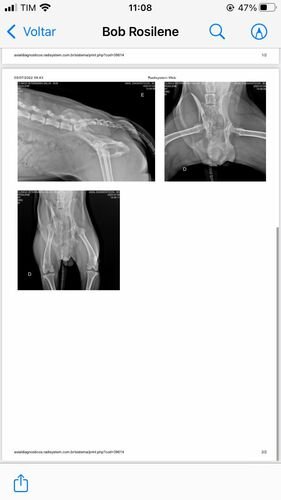

Bom, o Bob está com o quadril extremamente fraturado (conforme laudo disponível), inclusive o quadril dele está virado para o lado, ele precisa realizar um procedimento cirúrgico complexo e vai precisar utilizar placa (conforme foto do orçamento cirúrgico). Todos os custos de consulta e medicação eu consegui custear até agora (comprovantes disponíveis) mas infelizmente eu não consigo custear o valor da cirurgia em tão pouco tempo e peço ajuda de todos, todo valor é extremamente bem-vindo. Me ajudem a salvar a vida do Bob!

Laudo e Raio-x: